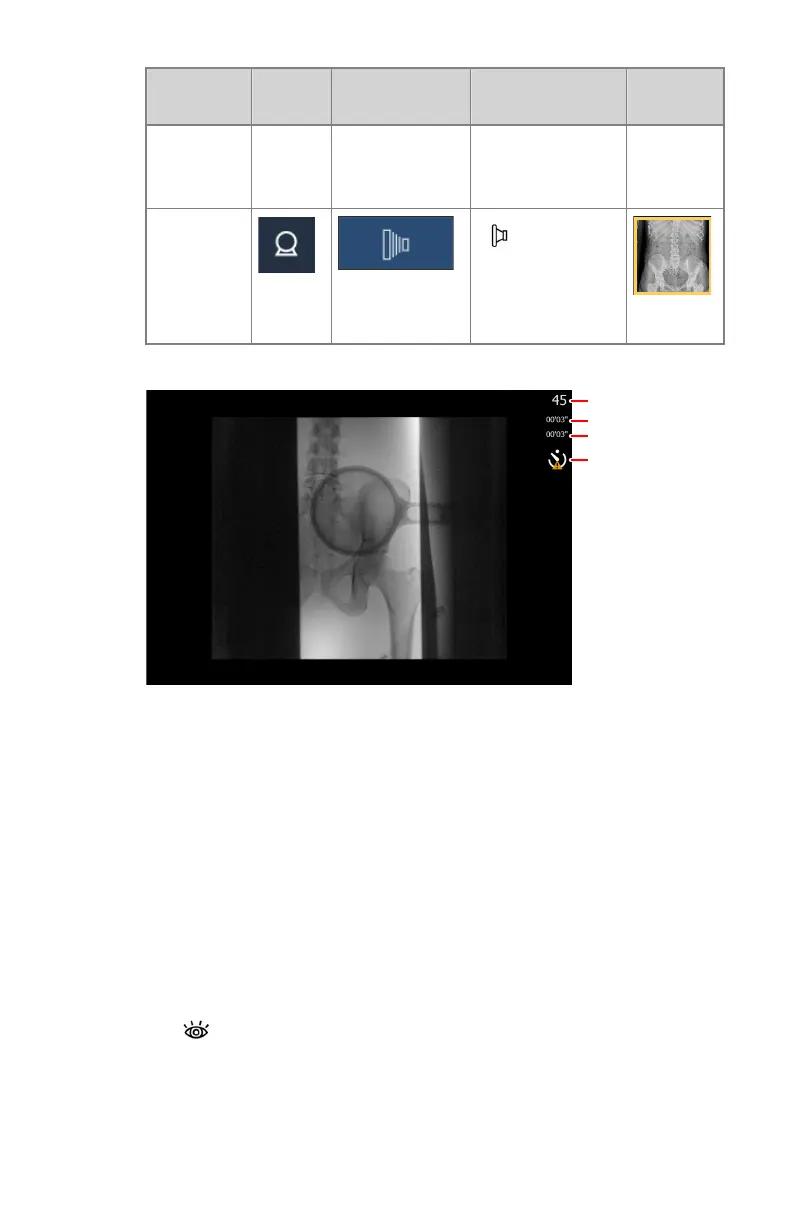

Information about the dynamic image is displayed next to the image.

1

2

3

4

1.

Current frame number

2.

Duration up till now of the current fluoroscopy or rapid sequence

exposure

3.

Total duration up till now of all fluoroscopy sequences in this

examination

4.

Warning sign for delay on real-time imaging

Figure 83: Dynamic image screen